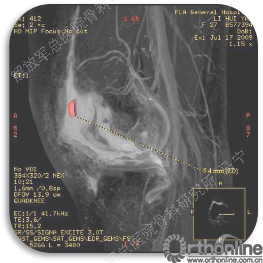

首先经过核磁的检查、评估,初步确定软骨损伤范围,利用T2maping检测序列对软骨的信号区分。图中我们可以看到软骨损伤的范围,并通过计算机计算出大概的面积。